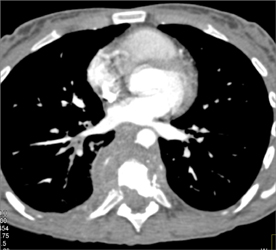

Diagnosis

Fusion of Bone